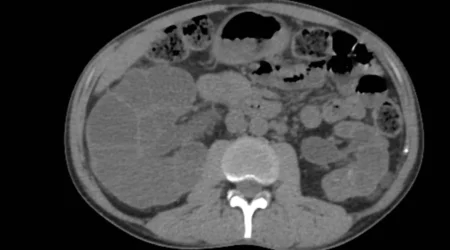

ألقى تقرير صحي جديد الضوء على حالة سلس البول، التي تُعد اضطراباً شائعاً يتمثل في فقدان السيطرة على المثانة والتسرب المستمر للبول، مشدداً على أن فهم الأنواع المختلفة للحالة هو مفتاح تحديد العلاج المناسب. ووفقاً لمصادر طبية، يتضمن العرض الرئيسي لسلس البول تسرب البول قبل الوصول إلى الحمام أو أثناء الأنشطة التي تزيد الضغط داخل…